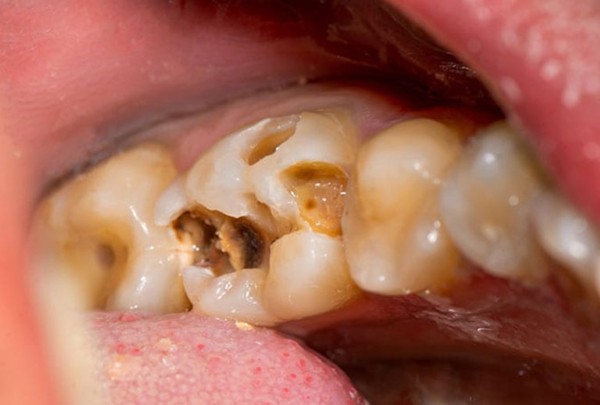

- Răng bị đổi màu, có vết đen hoặc lỗ sâu rõ rệt trên bề mặt.

Khi gặp các biểu hiện trên, bạn nên đi khám nha khoa càng sớm càng tốt để được kiểm tra và tư vấn. Nếu tổn thương quá nặng, không thể phục hồi bằng phương pháp trám hay điều trị tủy, bác sĩ có thể chỉ định nhổ răng hàm trên trong cùng bị sâu để tránh lây lan sang răng khác hoặc gây viêm nhiễm nghiêm trọng.